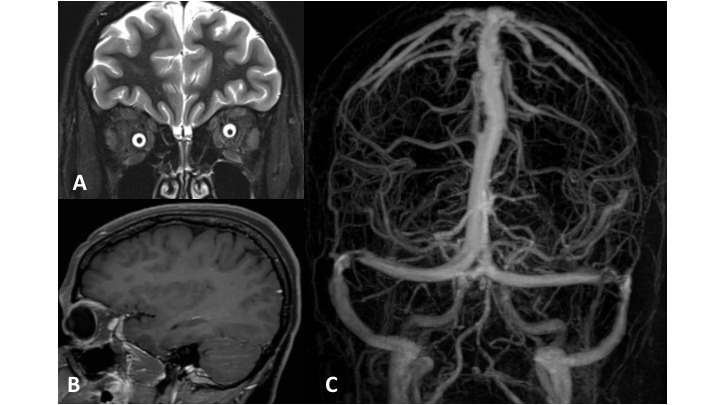

La thrombophlébite cérébrale est une des causes d’hypertension intracrânienne et on ne peut pas affirmer cette hypothèse diagnostique à ce stade. Seule l’imagerie complétée par un bilan biologique permettra de faire le diagnostic étiologique du syndrome d’hypertension intracrânienne.